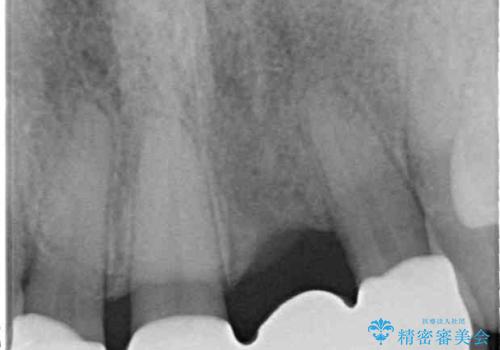

矯正治療により前歯横幅のバランスを整えた後に、上顎前歯をオールセラミックブリッジにて補綴治療を行うこととしました。

舌突出癖により、上下前歯が突出して離開してしまったため、舌のトレーニングを徹底的に行いました。